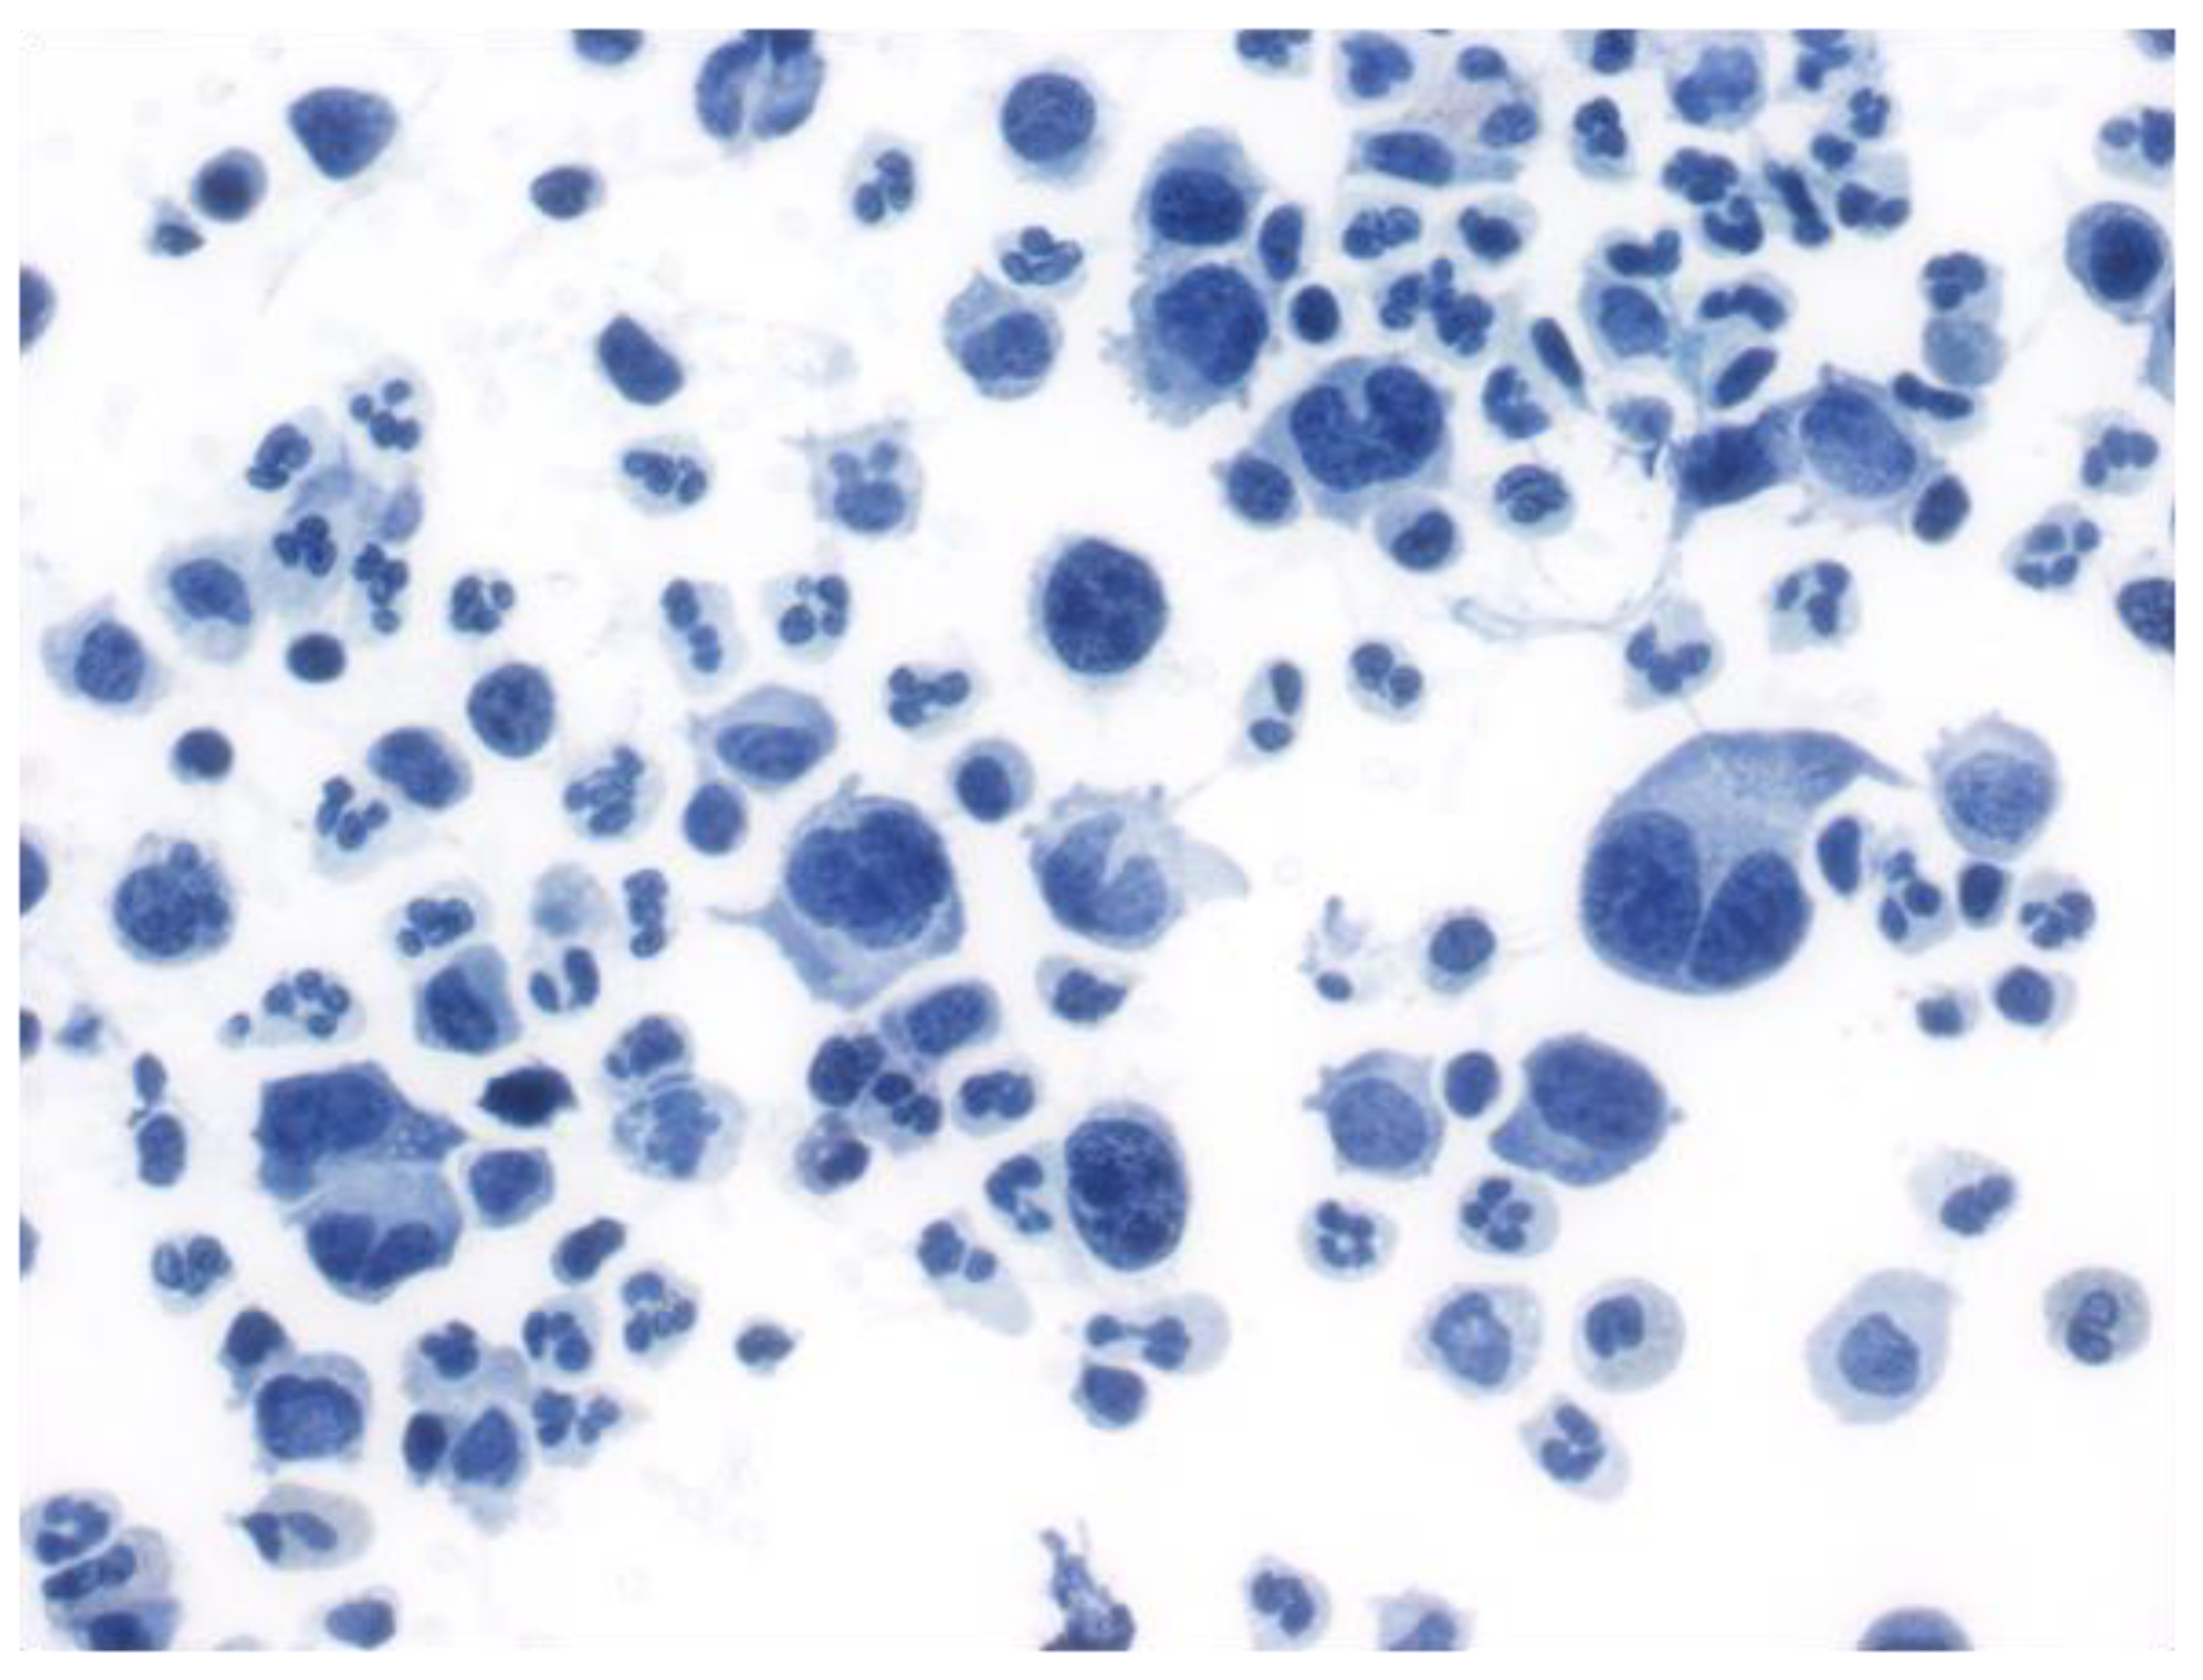

2.2. Follicular Lymphoma

5.2. Fluid Overload-Associated Large B-Cell Lymphoma (WHO Classification of Tumours of Haematopoietic and Lymphoid Tissues, 5th Edition; WHO-HAEM5)/HHV8 and EBV-Negative Primary Effusion-Based Lymphoma (International Consensus Classification; ICC)

5.3. High-Grade B-Cell Lymphoma with 11q Aberration (WHO-HAEM5)/Large B-Cell Lymphoma with 11q Aberration (ICC)

5.4. Double-Hit Lymphoma

5.5. Large B-Cell Lymphomas (LBCL) of Immune-Privileged Sites